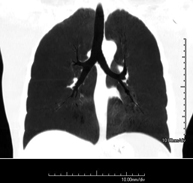

- TC Tòrax

Prova diagnòstica que consisteix en obtenir imatges del tòrax d'alta definició anatòmica (pulmons, cor, mediastí, grans vasos, caixa toràcica, etc. ) mitjançant l'ús d'un equip de TC (Tomografia Computeritzada). Aquestes imatges s'estudien posteriorment en una estació de treball que permet reconstruccions bidimensionals en diferents plànols de l'espai i també reconstruccions 3D (volumètriques). Alguns estudis requereixen l'ús de contrast iodat per millorar la definició de les imatges. - Angio –TC Aorta toràcica